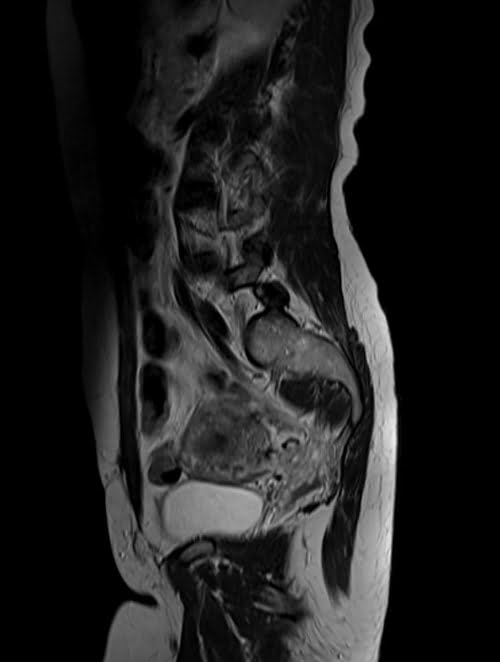

mri lumbosacral plexus sagittal t2 image 2 - MRI